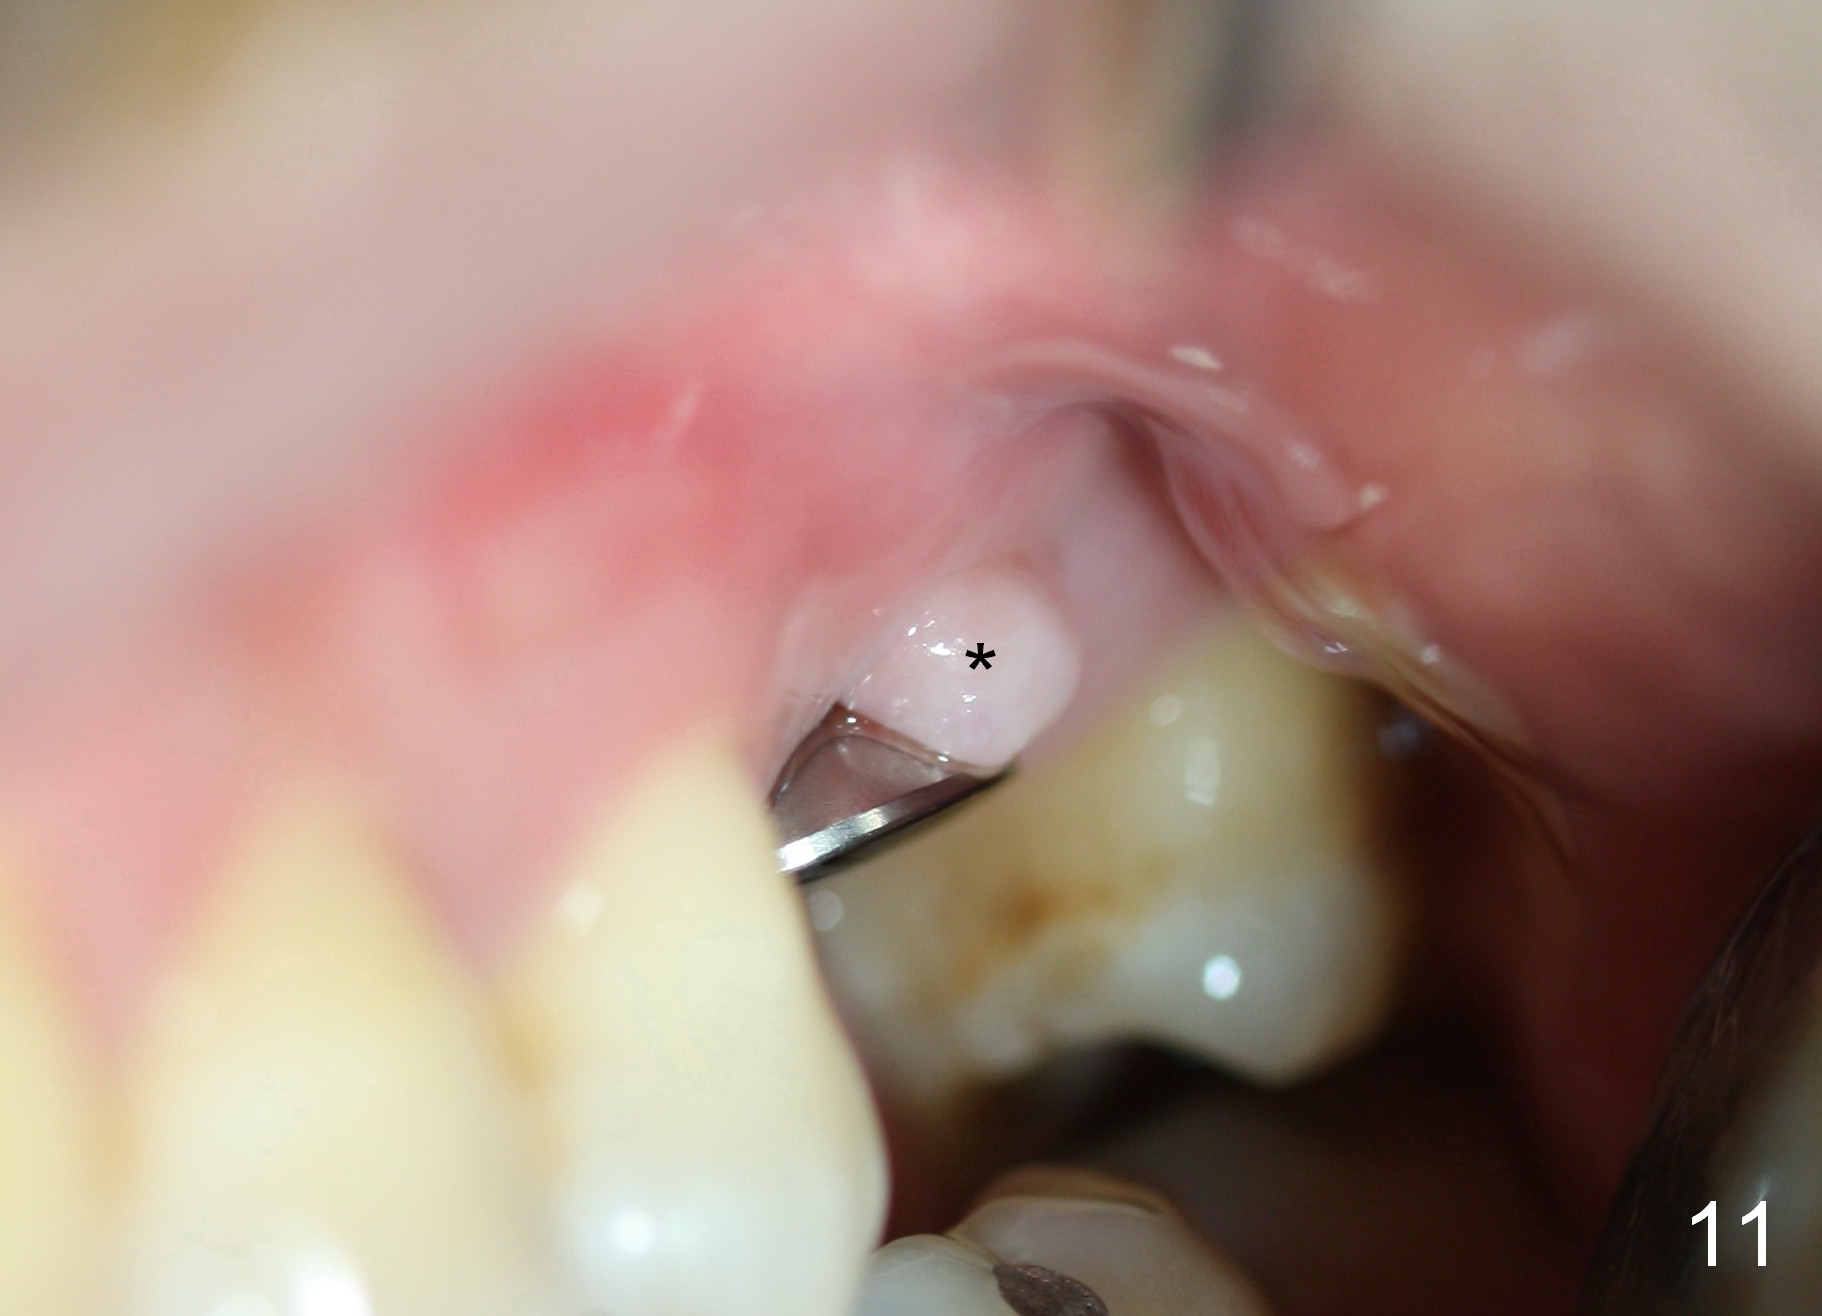

A 45-year-old man has lost the tooth #14 for a while (Fig.1); bone height is 5.4 mm. An extra wide and short implant is planned. Torus palatinus is large, suggesting that bone density should be high. A 6 mm tissue punch is chosen, but it is placed more palatal. If it were placed in the middle of the ridge, there would be no buccal keratinized gingiva (incision may avoid this issue). Additionally, the buccal portion of punch is made incomplete so that there is pedicle on the buccal side when the flap is raised (Fig.4,8: F). It is expected that the excess portion of keratinized tissue will form thick gingiva buccally. Osteotomy proves that bone is dense (Fig.2 (4.5x11 mm tap). Typical sinus lift is finished with placement of 6.4x6 mm (extra wide) bone-level implant (Fig.3, >55 Ncm). Following further torque, Fig.4 shows that the implant (I) is sub-gingival (<). Bitewings are taken to confirm that the implant plateau is at the crestal level (Fig.5,6 ^). PA shows sinus lift (Fig.7 *). The lingual aspect of the implant and healing abutment (H) is further bone grafted and covered by collagen dressing (Fig.8 *). The wound is protected with perio dressing. When the latter dislodges 7 days postop, the collagen dressing and bone graft are lost as well (Fig.10), while the buccal flap remains vital (Fig.9). The lingual exposed plateau should be able to heal normal. The collagen dressing should have been fixed in place by suture or as simple as a dental floss. There is mild nasal hemorrhage 1-2 days postop, possibly related to sinus membrane perforation and inability of Collagen Dressing to cover the perforation and contain the bone graft. When the patient returns for #9 implant placement in 3 weeks postop, the buccal flap reduces in size (Fig.11 *), while the palatal wound has healed with minimal exposure of the implant (Fig.12). Sinus graft remains in place 3 months postop (Fig.13); the buccal flap appears to have incorporated into a part of the gingiva (Fig.14). The bone density of the sinus lift appears to increase 10 days later when an abutment is placed (Fig.15 *). Although oral hygiene is pristine, there is apparent crestal bone resorption 12 months (Fig.16) and 20 months (Fig.17) post cementation, probably due to unfavorable crown/implant ratio and bruxism as well as pre-implantation bone loss (Fig.18,19). In contrast, an immediate implant in the same patient avoids pre- or post-implantation bone loss. In fact both the soft (Fig.20) and hard (Fig.21) tissues remain healthy 2 years 8 months post cementation. The sinus lift remains 3 years 8 months post cementation (Fig.22), while the crestal bone loss persists. The patients keeps complains of food impaction distal associated with bad smell 4 years 1 month post cementation. In fact the distal proximal contact is within normal limit. The bad smell is probably due to crestal bone loss (Fig.23 (pan), 24 (CT) *) and periimplantitis. Bone graft, PRF and Cytoplast membrane will be needed and fixed in place with long healing screw. When the patient returns for crown redo, he also reveals floss related gingival hemorrhage. There is pain associated with palatal sulcus probing with light gingiva erythema. Review of CT coronal section shows possible palatal (Fig.25 P) bone loss (*).